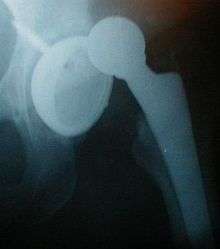

X-ray showing a joint dislocation of the left hip. | |